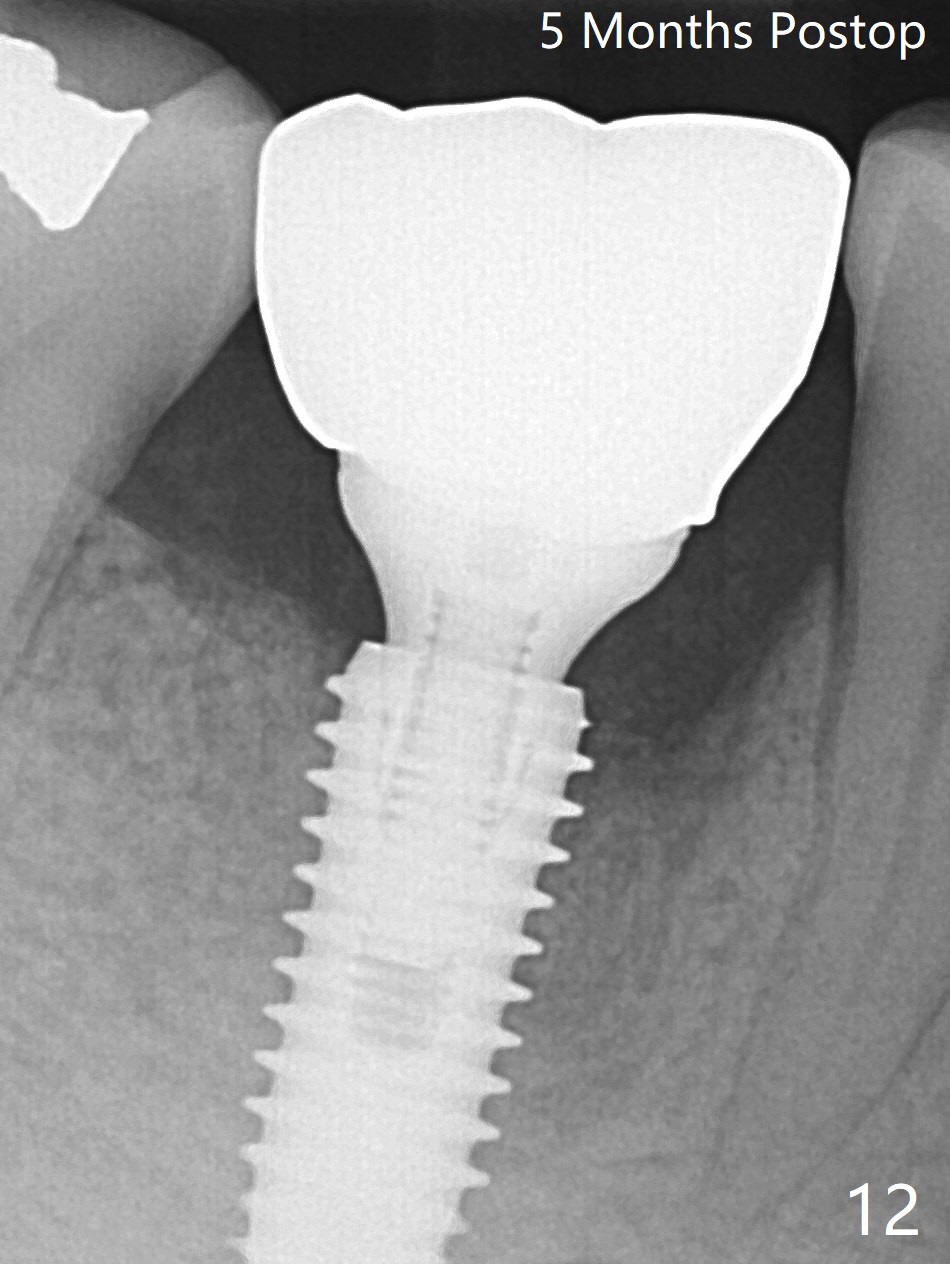

Preop oral Amoxicillin seems to be associated with reduction in the buccal and lingual (Fig.3 arrow) fistulae at #30, but there is mesiobuccal swelling (Fig.1 *) with 7 mm pocket (Fig.2). Osteotomy is initiated in the middle of the septum (Fig.3-5 S). As the osteotomy increases, it shifts mesially (Fig.6 arrow). Guided surgery is able to reduce shifting. A 5x13 mm implant is not seated completely (Fig.7) apparently due to osteotomy shifting. After removal of the bone from the osteotomy distally, the implant remains unseated with lower torque value (Fig.8). Following reuse of the 4.3 mm drill deeper by 1-2 mm, the implant is seated to a satisfactory depth (Fig.9 with increase in torque to 50 Ncm) with placement of Vera Graft (*) and a 7.5x4(3) mm abutment. After a second round of allograft placement (Fig.10 *), the implant is found to be 4 mm from the IAC. At the later stage of osteotomy, the coronal end of the septum is destroyed with loss of osteotomy depth landmark. It is apparent that the soft tissue landmark may be more reliable. The implant threads appear to be covered by the bone graft 3.5 months postop (Fig.11). The abutment is changed to 6.5x5(3) mm one before impression with minor margin prep. The bone density seems to increase 5 months postop, i.e., immediately post cementation (Fig.12) and 10 months postop (5 months post cementation (after retightening abutment), Fig.13 (*)). Periimplantitis develops mesiobuccally, consistent with bone loss 1 year 7 months post cementation (Fig.14 *); the implant seems to have been buccally placed. Bone graft is necessary with PRF or GEM21S if the vein is small and 6-month membrane with a hole around a 7.5x4(4) cemented abutment for easy wound closure. Take 5x5 CM CBCT to determine which wall has defect, buccal or lingual. Check mesial contact. If so, remove the crown, reseat the abutment (possible incomplete seating) and re-impress after bone graft.